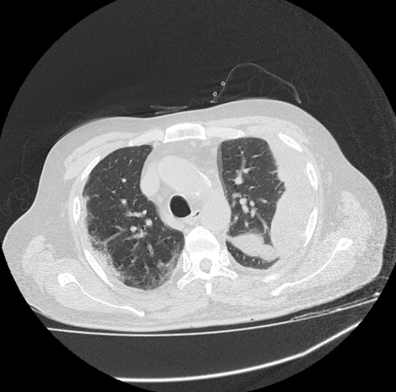

This image of the patient is with ground-glass opacities with the symptoms of milk short breath and fever. The figure 1 shows the day 1 imaging, in which the septal thickness is mild, as the symptoms grow to day 3, the thickness in found to be higher in the lungs of the patient, whereas a rise in ground-glass opacities is also observed.

Figure 1 Day 1 CT imaging.